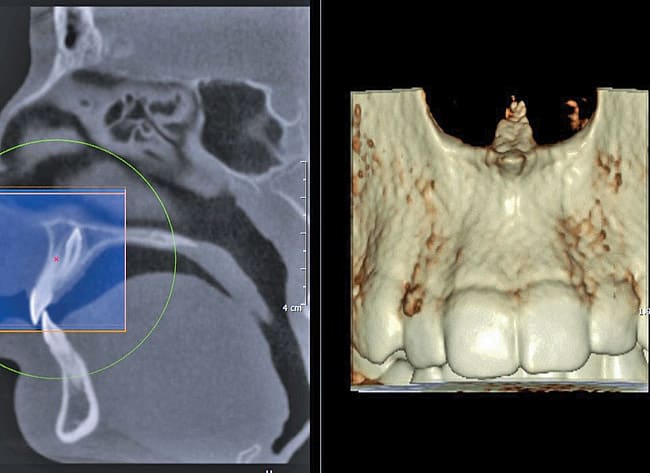

Finally, whether clinicians purchase or simply use the data from CBCT machines in their practice, it is important—perhaps imperative—that they obtain training beyond the manufacturer’s hands-on, in-office introduction. Until trained, a dentist or dental specialist is simply not used to seeing a patient image in the axial plane of section. These types of images, as well as the images in the coronal and sagittal planes and the anatomic data within them, must be mastered before a clinician can feel comfortable using CBCT (Figure 1, Figure 2, and Figure 3).